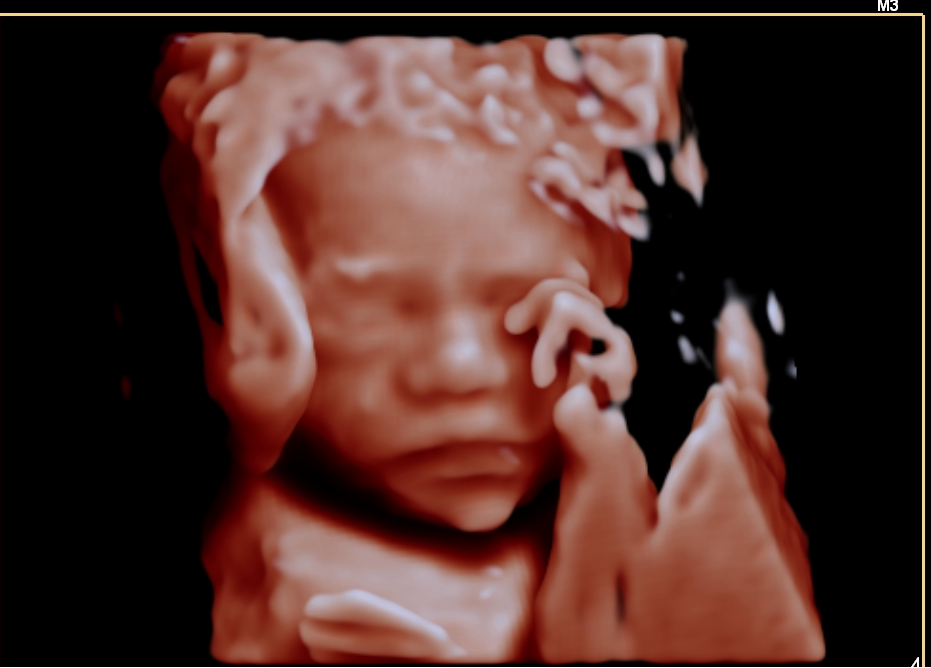

四维彩超就像是给宝宝在子宫里拍的一段 “动态3D电影” 。它能够让准爸爸准妈妈们清晰地看到宝宝在肚子里的实时动态,比如打哈欠、吃手指、微笑、翻身等,为孕期增添了许多惊喜和温情。

2. 次要目的:满足情感需求

让准父母亲眼看到宝宝的活动,建立早期的亲子连接。可以拍摄照片和视频,作为一份珍贵的纪念。